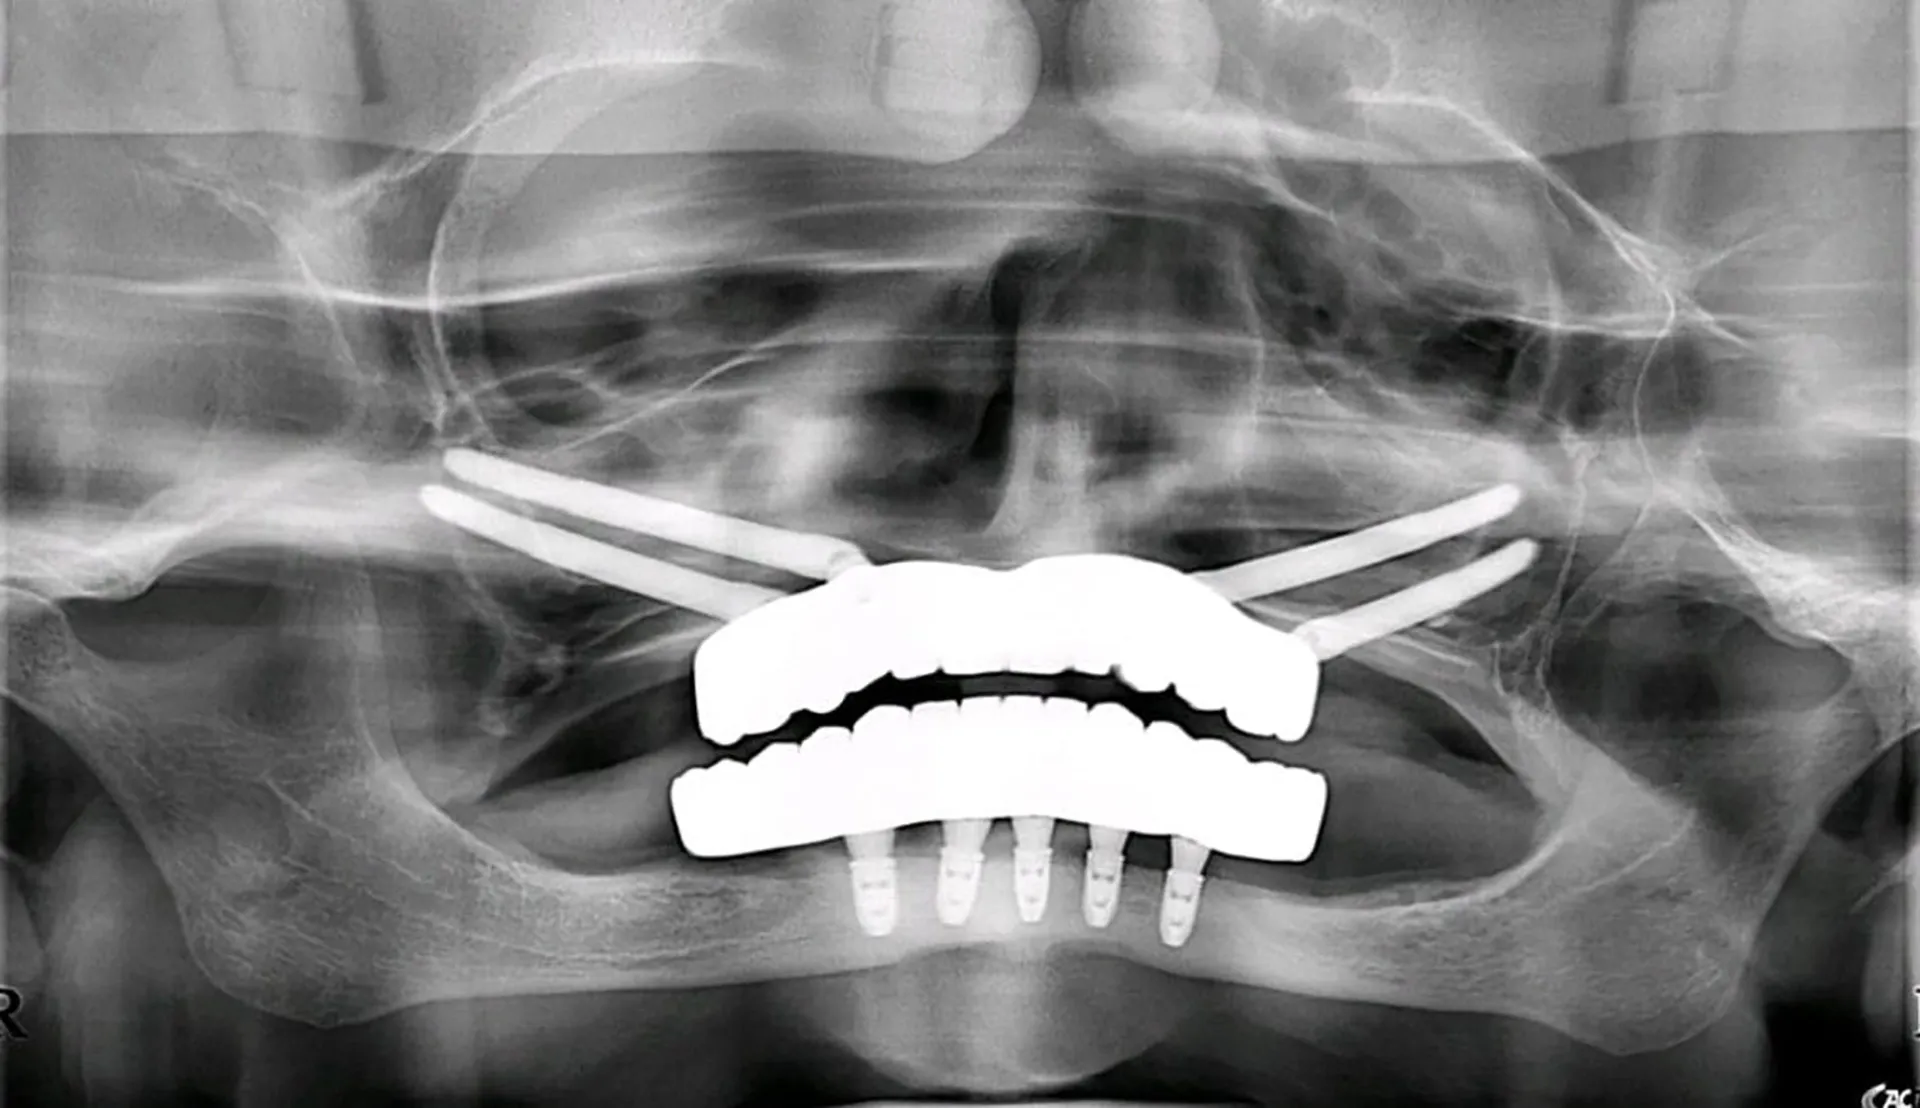

Behind every restored smile, there is precise planning. These radiographic studies show how advanced imaging and implant techniques allow us to transform even the most complex cases into stable, long-term solutions.

Our innovative techniques, including zygomatic and pterygoid implants, anchor directly into your natural bone structure, creating a strong and lasting foundation for fixed, beautiful teeth — even in the most complex cases.

Zygomatic Implants

The main purpose of zygomatic implants is to offer a fixed, functional, and aesthetic prosthetic solution.

Pterygoid Implants

Posterior support without sinus grafts. Pterygoid implants offered at our Costa Rica clinic.